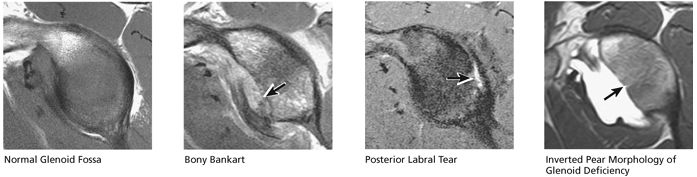

identified. In patients with a history of recurrent dislocations, a sagittal image through the glenoid demonstrates deficiency of the anterior inferior glenoid, manifested as bony Bankart fractures through the anterior inferior glenoid or remodeling and attrition of the anterior inferior glenoid, resulting in an “inverted pear” appearance. Subchondral cystic changes in the glenoid are seen as focal high-signal areas within the glenoid, suggesting overlying chondromalacia.

At the lateral angle of the scapula is the glenoid cavity (glenoid fossa) with its supraglenoid and infraglenoid tuberosities. The glenoid version angle varies and may contribute to instability patterns of the shoulder.